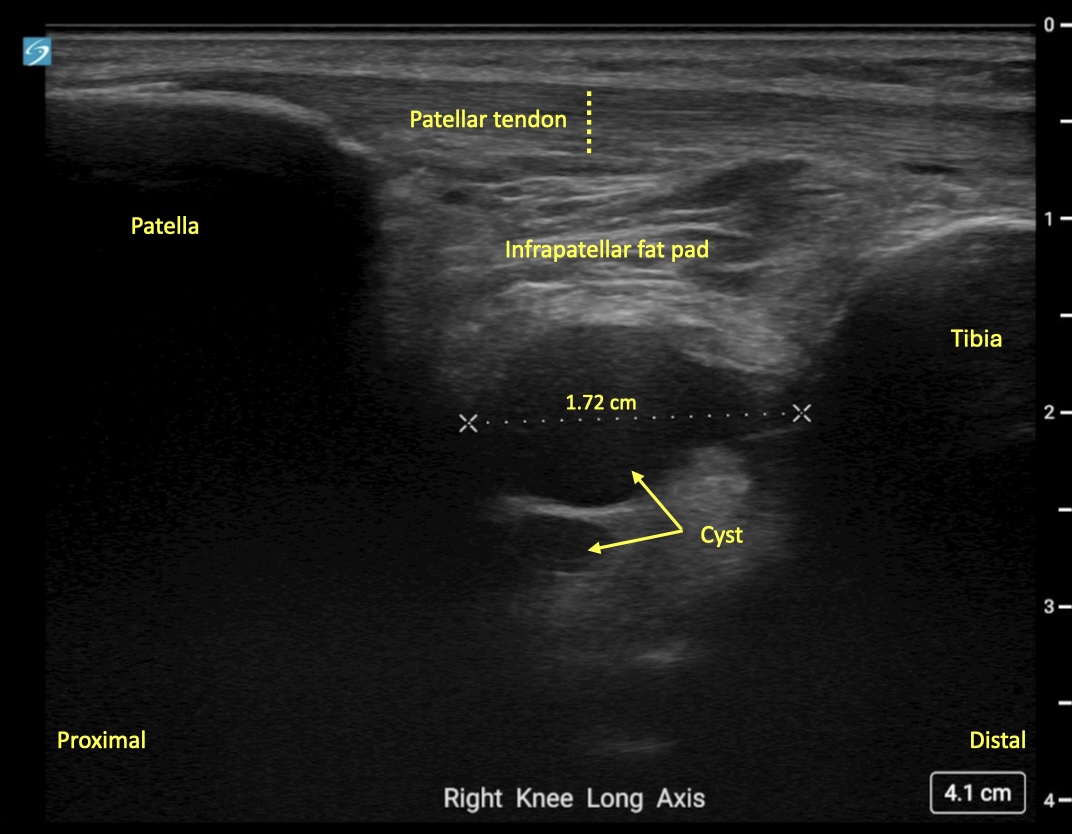

Image Interpretation: An anechoic, well-circumscribed, well-demarcated mass was noted deep to the infrapatellar fat pad. This measured 2.02 cm x 1.08 cm x 1.72 cm. No color Doppler flow was noted and the structure remained noncompressible when pressure was applied. A separate, smaller, anechoic mass was noted deeper to this structure and likely communicated with it. Findings were consistent with a multiloculated cyst of intra-articular origin.

MRI was subsequently performed with findings of chronic high grade partial ACL tear with mucoid degeneration of the ACL and multilobulated ganglion cyst originating from the anteriorly from the ACL at the intercondylar notch, correlating well with ultrasound findings.